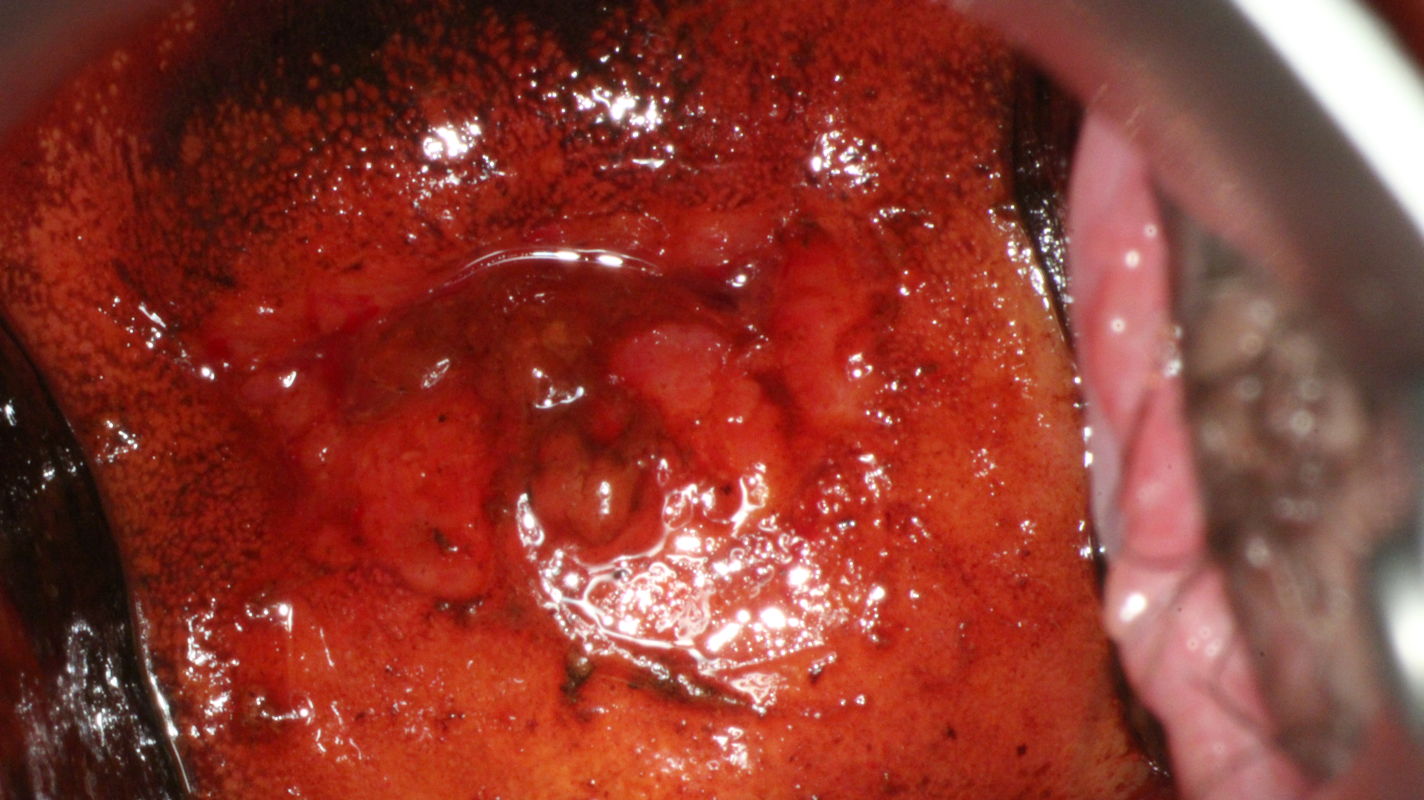

Though described in the IFCPC classification as a nonspecific colposcopic criterion, the degree of iodine uptake can provide a useful graduating sign at colposcopy. Colposcopic findings in a 37-year-old gravida 2, para 2 who has experienced contact bleeding for several months are presented. Her smear was reported as class II-a. HPV DNA was not detected. Colposcopy shows partial iodine uptake in a typical T-zone type 2, which is classified as a normal colposcopic finding.

Histopathology of tissue sampled at 6 o’clock by strip biopsy shows normal endocervical crypt (glands) surrounded by normal stromal tissue. The findings are interpreted as normal.